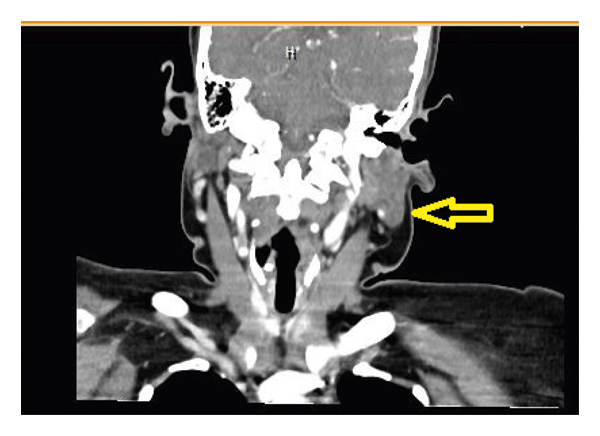

This is a 58-year-old female with a past medical history of Diabetes Mellitus and asthma who presented for evaluation of hypercalcemia. The patient was referred from the Primary Care Physician’s office after routine blood work revealed elevated calcium levels. Of note, the patient visited her primary care physician for evaluation of cough and dyspnea one month prior; encounter during which a chest roentgenogram revealed left lobe enlargement with right tracheal deviation. She underwent a subsequent computed tomography (CT) of neck soft tissue which revealed 3.5 centimeters nodule of the left thyroid gland (Figure 1). A fine needle aspiration of the nodule revealed a Bethesda category II, benign. However, the specimen was marginally adequate. She was also diagnosed with hypothyroidism and levothyroxine was initiated. She reported a globus sensation for the past 2 months prior to our encounter. She also reported abdominal pain associated with constipation for the past week prior to our encounter. She denied any dysphagia or change in voice.

Upon arrival in the Emergency Department, she was hemodynamically stable. A left thyroid nodule with cervical lymphadenopathy could be felt on physical examination. Her laboratory results revealed an elevated serum calcium, higher normal 1,25(OH)2 vitamin D and lower normal 25(OH) vitamin D, and an elevated Angiotensin Converting Enzyme level, as seen in Table 1. A CT of the chest and abdomen revealed mediastinal and hilar lymphadenopathy (Figure 2) and multiple nodules of the liver and spleen (Figure 3). A subsequent biopsy of the liver revealed granulomatous hepatitis consistent with sarcoidosis.